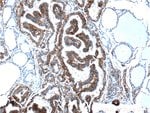

PKC alpha Rabbit anti-Human, Mouse, Polyclonal, Proteintech

| Applications | Immunohistochemistry (Paraffin), Immunofluorescence, Immunocytochemistry, Western Blot, Immunoprecipitation |

Protein kinase C (PKC) is a family of serine- and threonine-specific protein kinases that can be activated by calcium and the second messenger diacylglycerol. PKC family members phosphorylate a wide variety of protein targets and are known to be involved in diverse cellular signaling pathways. PKC family members also serve as major receptors for phorbol esters, a class of tumor promoters. Each member of the PKC family has a specific expression profile and is believed to play a distinct role in cells. The protein encoded by this gene is one of the PKC family members. This kinase has been reported to play roles in many different cellular processes, such as cell adhesion, cell transformation, cell cycle checkpoint, and cell volume control. Knockout studies in mice suggest that this kinase may be a fundamental regulator of cardiac contractility and Ca(2+) handling in myocytes.Specifications

| Immunohistochemistry (Paraffin), Immunofluorescence, Immunocytochemistry, Western Blot, Immunoprecipitation | |